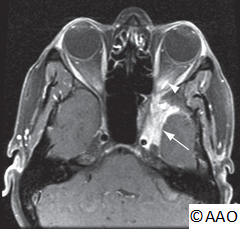

Neuroimaging studies should be performed for patients suspected of having the Foster Kennedy syndrome (e.g., head and orbital CT or MRI with and without contrast).

- Atypical cases should undergo consideration for neuroimaging (CT and MRI) to rule out intracranial mass, optic nerve enhancement